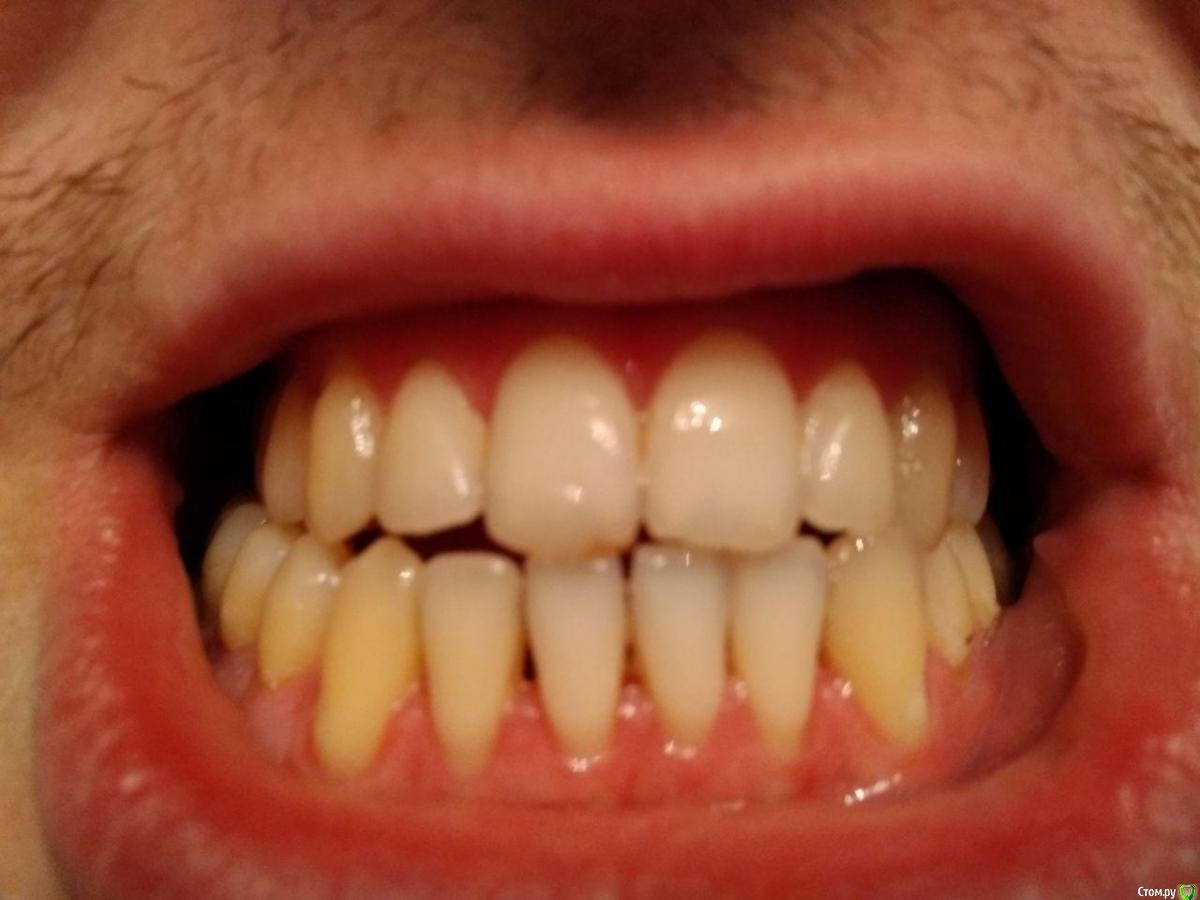

Здравствуйте, мне 29 лет, хочу остаться со своими зубами и не угробить ВНЧС.

С 16-20 лет проходил лечение у ортодонта (2 года расширитель на верхней челюсти, 2 года брекеты). Итог - получили, так называемый камуфляж (как я сейчас понимаю).

В данный момент ситуация усугубилась, основные проблемы - множественные рецессии и хруст в ухе при глотании.

2 ортодонта посоветовали два разных подхода к лечению:

1ый Операция и только она. На вопрос поможет ли это устранить рецессию, был ответ, что вам никто не скажет, но для проведения операции нужно будет вернуть все зубы в прежнее положение.

2ой Провел диагностику, ТЭНС терапию, сделал капу на нижнюю челюсть (хруст при зевании прекратился, при глотании все равно слышно), про  рецессию было сказано, что некоторые зубы получают неправильную нагрузку, но причина именно множественной рецессии не в прикусе. Дальнейшие предложении - устранение перекрестного прикуса с помощью брекетов или оклюзионного протокола.